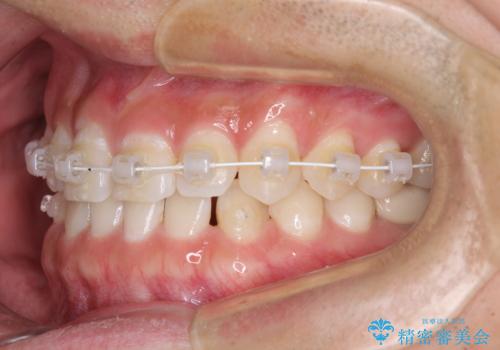

- 矯正装置

- 審美装置

- 1年1ヶ月

- 10-30回